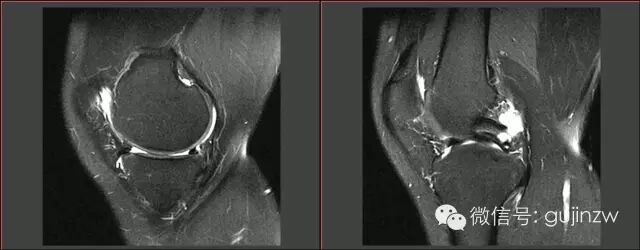

MRI常见征象

• 直接诊断半月板损伤:3度损伤,半月板形态异常,半月板与关节囊分离。

• 征象:蝴蝶结缺失征,多蝴蝶结征,双后叉征。

3度损伤

半月板形体异常、与关节囊分离

蝴蝶结缺失

双后叉征

多蝴蝶结征